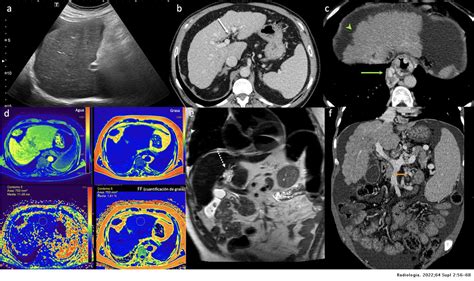

In addition to conventional ultrasound, advanced techniques can enhance the diagnostic capabilities of Parenquima Hepatico Izquierdo Ecografia. These include:

• Doppler Ultrasound: Uses sound waves to measure blood flow and detect vascular abnormalities.

• Contrast-Enhanced Ultrasound (CEUS): Involves the use of contrast agents to improve the visibility of liver lesions and vascular structures.

• Elastography: Measures the stiffness of liver tissue, helping to assess the degree of fibrosis and cirrhosis.